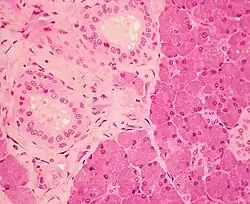

Stratified cuboidal epithelium, highlighting the nucleuses, the rest of the epithelial cells, and underlying connective tissue.

Stratified cuboidal epithelium is a type of epithelial tissue composed of multiple layers of cube-shaped cells. Only the most superficial layer is made up of cuboidal cells, and the other layers can be cells of other types. Topmost layer of skin epidermis in frogs, fish is made up of living cuboidal cells.

This type of tissue can be observed in sweat glands, mammary glands, circumanal glands, and salivary glands.[1][2] They protect areas such as the ducts of sweat glands,[3] mammary glands, and salivary glands. They are also observed in the linings of urethra.